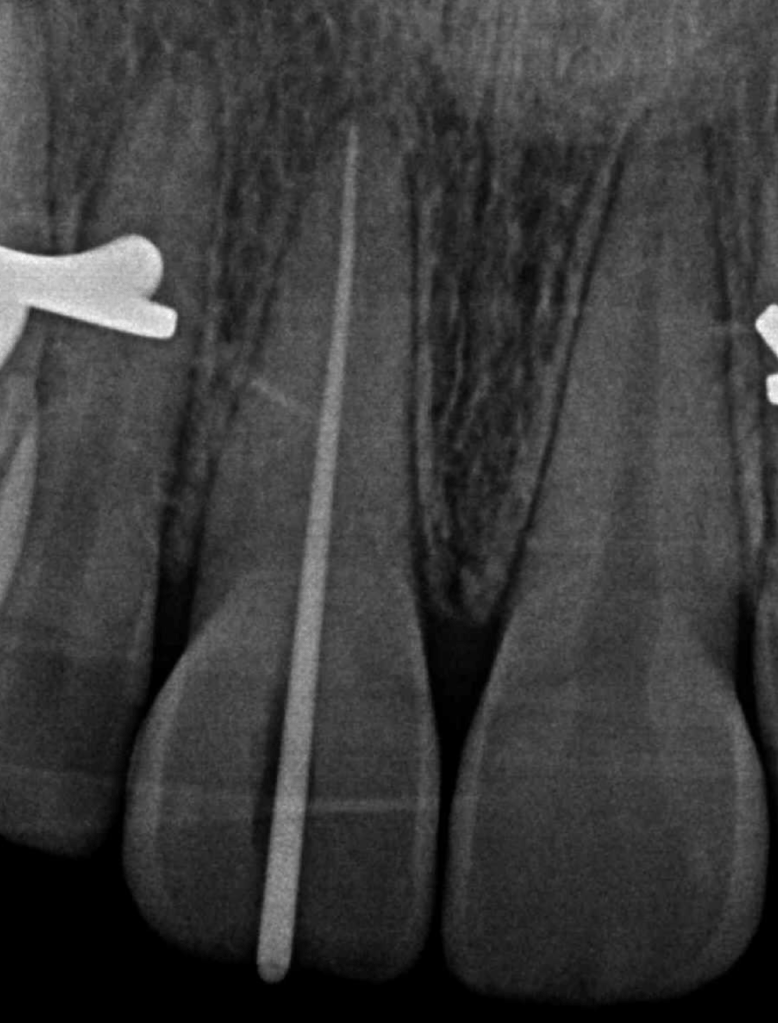

2 Limas rotas + reco Preendo

Lima en conducto MV